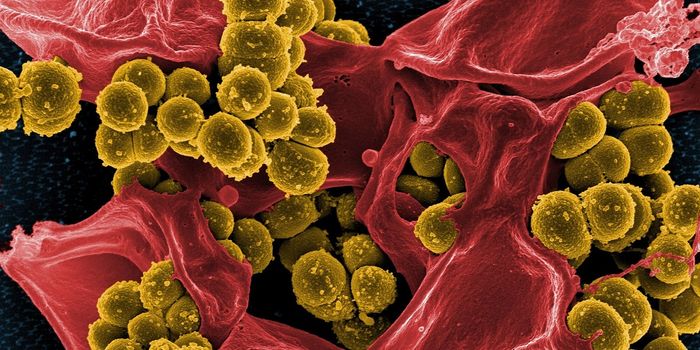

OCT 29, 2016Clinical & Molecular DXDespite frequent cleaning and sterilization, hospitals are notorious hotspots for germs and pathogens. And it’s no ...

MAR 10, 2021Clinical & Molecular DXMicrobiologists have discovered that the types of bacteria on a dermatitis patient’s skin affect the severity of t ...

SEP 20, 2023Clinical & Molecular DXHospitals are supposed to help sick people get healthy, but unfortunately, many hospitalized patients become sick with i ...

MAR 19, 2017MicrobiologyIt can be incredibly challenging to give a patient the proper treatment when they are infected by an antibiotic-resistan ...

APR 13, 2022MicrobiologyApply the learnings of COVID to AMR, says coalition Tackling the deadly spectre of antimicrobial resistance (AMR) requir ...

OCT 18, 2019Health & MedicineMultidrug-resistant bacteria are frequently found in hospitals and long-term nursing facilities causing one of the large ...

AUG 23, 2022MicrobiologyWith effort, we all can help counter the rise of bacterial pathogens that resist the effects of multiple antibiotics.